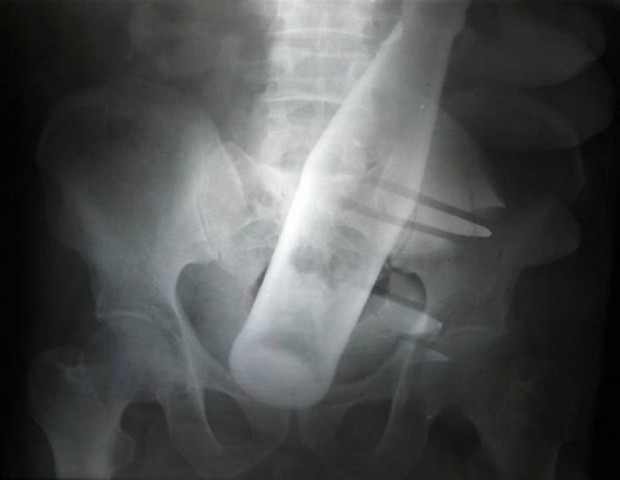

20. Бутылка из-под «Пепси» в анусе 60-летнего мужчины.